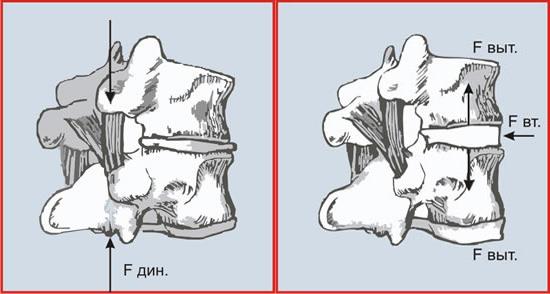

Поврежденные межпозвонковые диски со временем теряют свои эластичные свойства, уплощаются, и расстояние между позвонками уменьшается. А это, значит, что отходящие от спинного мозга нервные корешки зажимаются, возникает боль. Одновременно в области зажима нервно-сосудистого пучка появляется отек, что приводит к еще большему его ущемлению и усилению боли.

3. Уникальным методом купирования болей в спине является также вытяжение на аппарате «ОРМЕД». Вытяжение осуществляется дозировано, проводится 10-12 процедур, при наличие противопоказаний применяется мягкое вытяжение поясом "Эртрак".

Преимущества консервативного лечения межпозвоночной грыжи:

-Осуществляется разгрузка позвоночника, путем увеличения расстояния между позвонками;

-уменьшаются мышечные контрактуры;

-снижается внутридисковое давление;

-увеличивается вертикальный диаметр межпозвонкового отверстия, что ведет к декомпрессии корешка и уменьшению отека;

-устраняется подвывих межпозвонковых суставов, что дает декомпрессующий эффект.

Уникальным методом купирования болей в шее является также вытяжение на аппарате «ОРМЕД». Вытяжение осуществляется дозировано, проводится 10-12 процедур, при наличие противопоказаний применяется мягкое вытяжение воротником "Эртрак".

3. Уникальным методом купирования болей в спине является также вытяжение на аппарате «ОРМЕД». Вытяжение осуществляется дозировано, проводится 10-12 процедур, при наличие противопоказаний применяется мягкое вытяжение поясом "Эртрак".